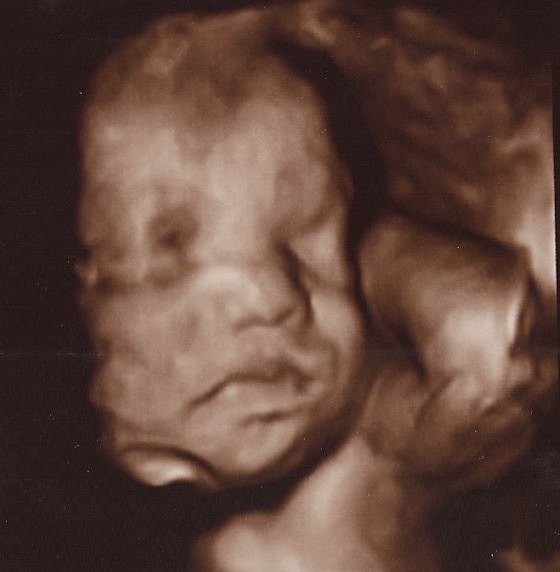

Det er så vildt at være til 3D scanning, det er som om, man er gravid på en helt anden måde bagefter

Ja, virkelig! Det er en hel anden måde at forholde sig til den lille på! Men når man ser billederne synes jeg man tænker "iih hun er stor", men hun er jo i virkeligheden stadig lillebitte. Lidt skægt